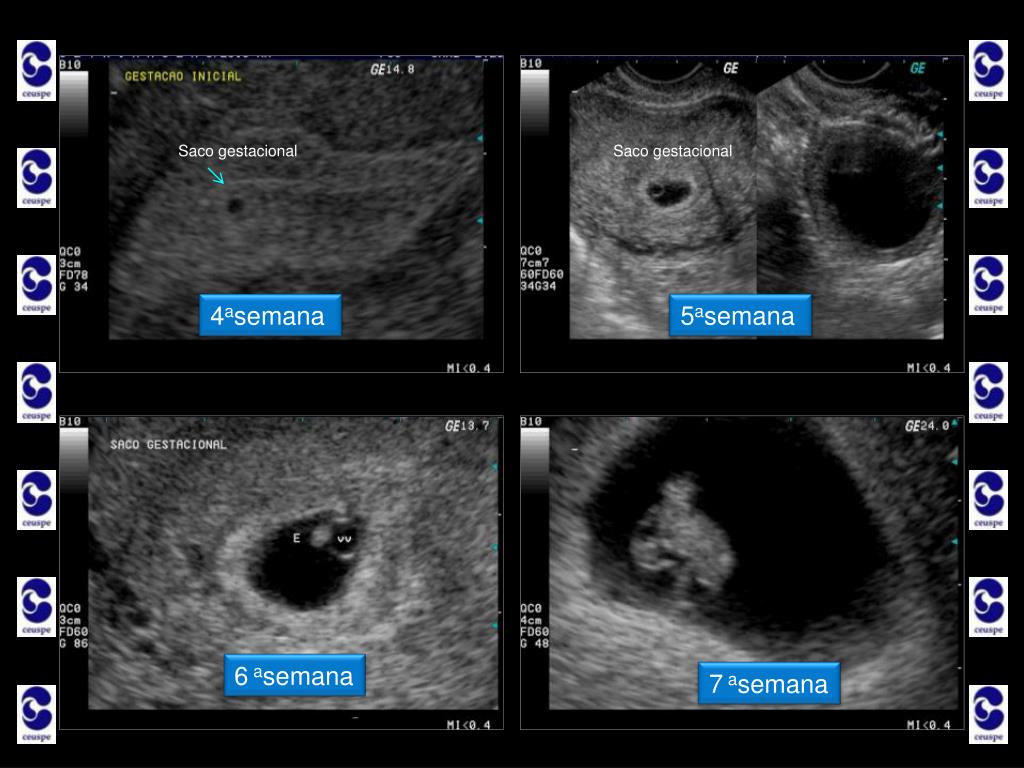

5. Ultrassonografia nos primeiros três meses... • Primeiro Trimestre • Idade Gestacional • geralmente quando o exame de beta-hCG passa de 1.000mU/ml é possível encontrar o saco gestacional no interior do útero. Estamos então na quarta semana de gravidez; • dentro do saco gestacional, surge uma “bolinha” de líquido chamada vesícula vitelina que alimenta o pequenino embrião que ainda não é visível pela ultrassom, mas já está por lá! É como se essa “bolinha” fosse a estrela de Belém, que anuncia a chegada do novo ser! Já estamos na quinta semana; • na sexta semana, o embriãozinho surge com 5mm de comprimento piscando...É o pequeno coraçãozinho já batendo...

9. Saco gestacional Saco gestacional 4asemana 5asemana 6asemana 7asemana